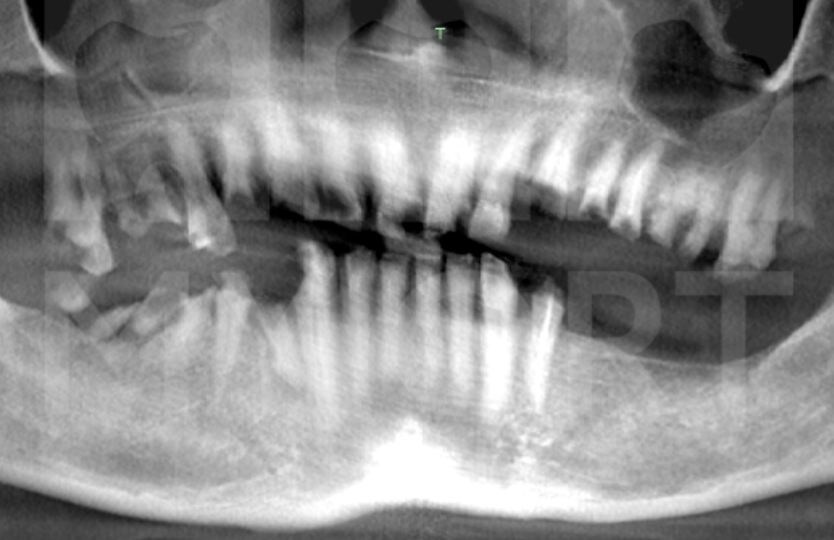

Осмотр полости рта и компьютерная томография показали, что большинство зубов разрушены и не подлежат восстановлению. Также отмечались очаги хронической инфекции. Костная ткань была сохранена неравномерно, особенно в области верхнечелюстных пазух. Опорных зубов, пригодных для протезирования, обнаружено не было.

Неравномерная костная ткань в области верхнечелюстных пазух

Благодаря точному планированию удалось избежать синус-лифтинга (костной пластики в области дна верхнечелюстной пазухи справа).

Через 3 месяца после имплантации была проведена контрольная компьютерная томография (КТ), которая подтвердила стабильность всех 11 имплантатов.